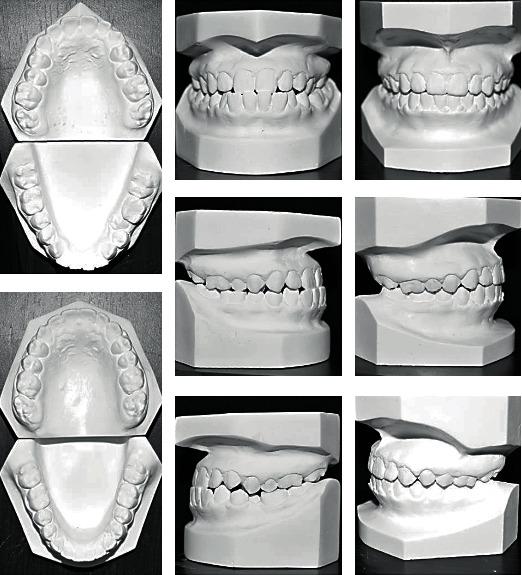

Distalization is a conservative method that is utilized in orthodontics to gain space by moving posterior teeth distally. It may be combined with other space gaining strategies, such as expansion, or can be used alone. Many methods have been used for distalization. These methods differ significantly in their place, whether to be extraoral or intraoral, site of action in upper and/or lower arch, and cooperation needed by the patient if it is removable or fixed. This review illustrates some of the most commonly used methods for distalization with a brief presentation of three cases that incorporated successful distalization techniques.